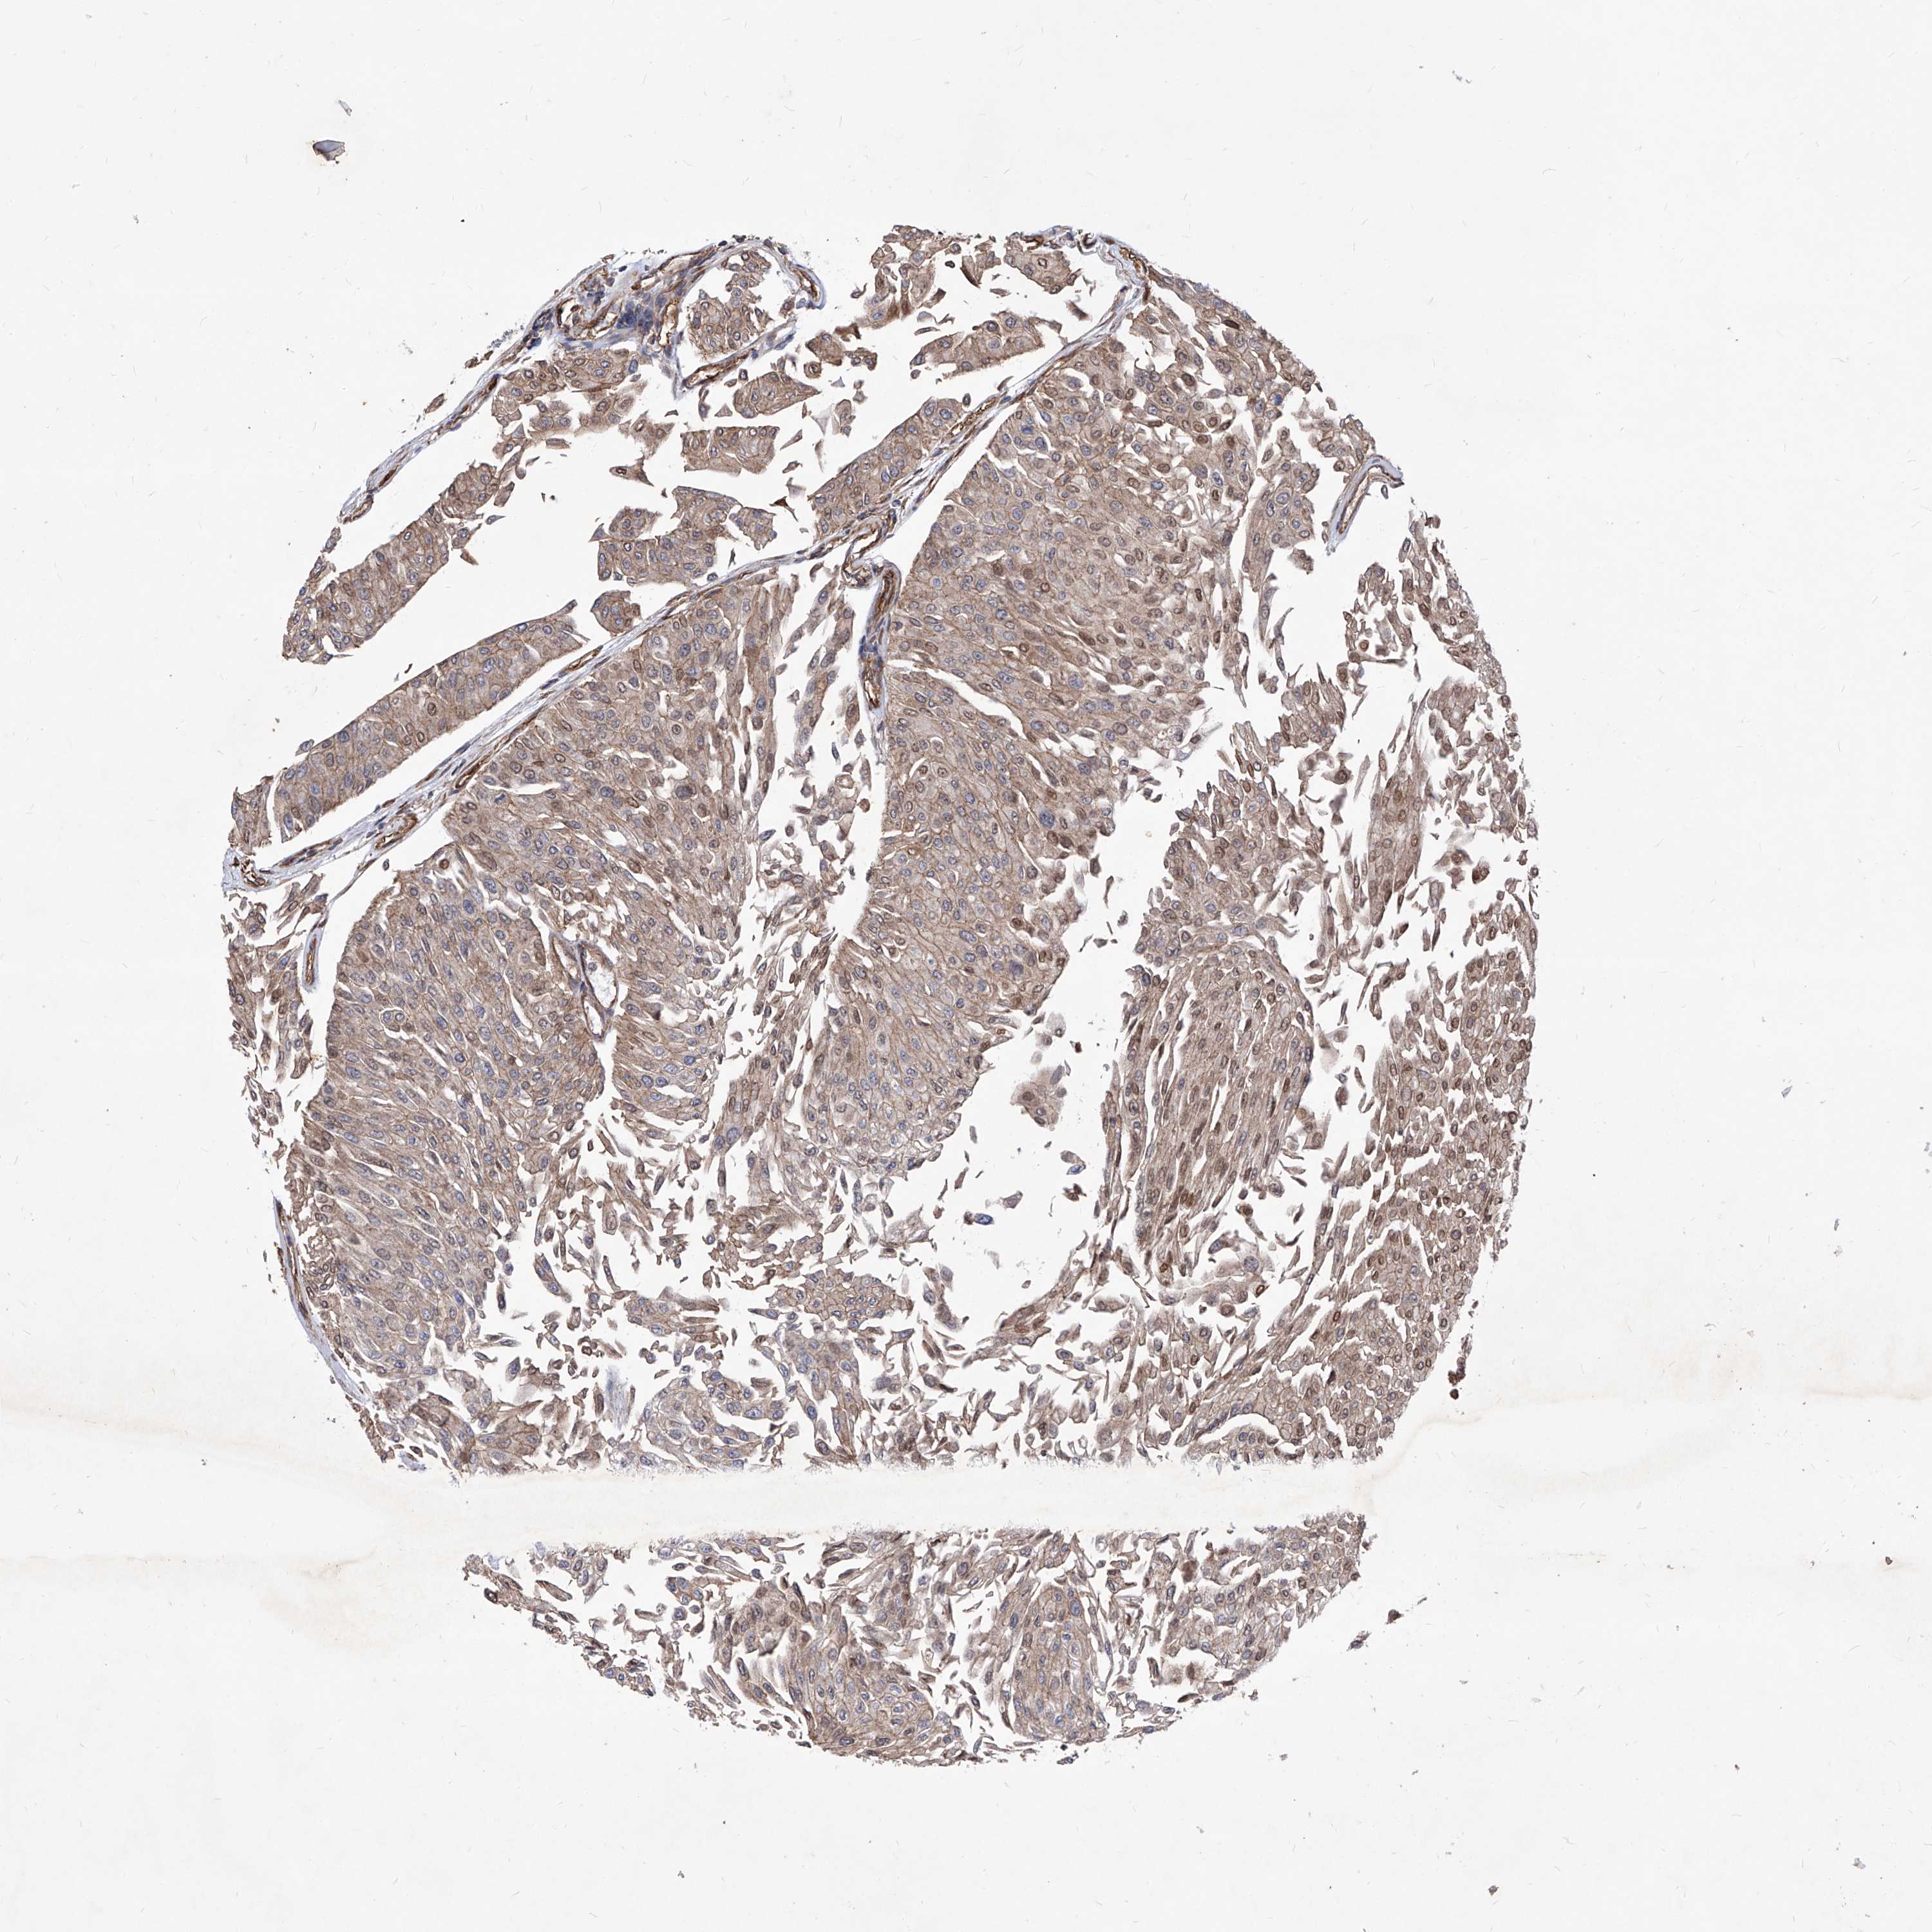

UROTHELIAL CANCER - Protein expressioni

A mouse-over function shows sample information and annotation data. Click on an image to view it in a full screen mode. Samples can be filtered based on level of antibody staining by selecting one or several of the following categories: high, medium, low and not detected. The assay and annotation is described here.

Note that samples used for immunohistochemistry by the Human Protein Atlas do not correspond to samples in the TCGA dataset.

Antibody stainingi

Antibody staining in the annotated cell types in the current human tissue is reported as not detected, low, medium, or high, based on conventional immunohistochemistry profiling in selected tissues. This score is based on the combination of the staining intensity and fraction of stained cells.

Each image is clickable and will lead to virtual microscopy that enables deeper exploration of all samples and also displays staining intensity scores, fraction scores and subcellular localization as well as patient and tissue information for each sample.

Antibody HPA029534

Staining

High

Medium

Low

Not detected

Intensity

Strong

Moderate

Weak

Negative

Quantity

>75%

75%-25%

<25%

None

Location

Nuclear

Cytoplasmic/membranous

Cytoplasmic/membranous,nuclear

Urothelial carcinoma, Low grade

Urothelial carcinoma, High grade